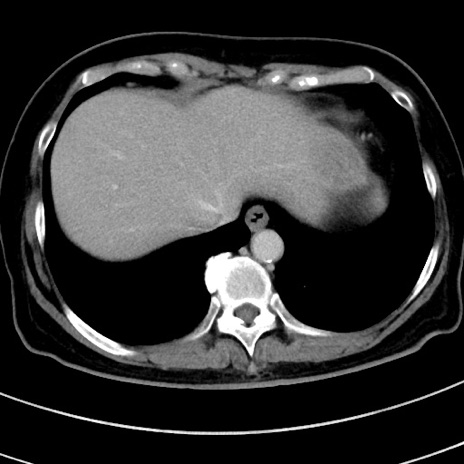

症例9(横断像)

【症例】 60歳代女性

【主訴】むかつき、みぞおちの痛み

【現病歴】3日前よりむかつきがあり、食事がとれない。

【既往歴】糖尿病

【身体所見】発熱なし、心窩部圧痛軽度あるも、腹膜刺激症状なし。

【データ】WBC 7400、CRP 1.92